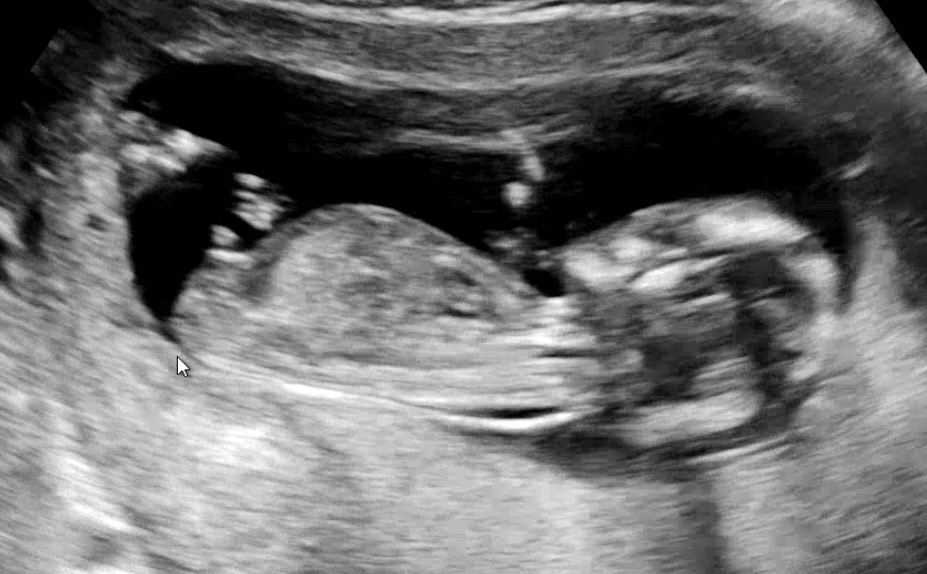

12주 6일 각도법 부탁드려요

의사선생님은 아들일것같다고 하는데 각도법으로는 딸이라고 하고 잘 모르겠네요